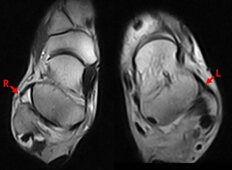

在外踝韧带损伤时,应力位摄片和磁共振(MRI)影像研究进展迅速,这为准确诊断和确定治疗方案创造了条件。应力位的摄片对于可靠地判断韧带是否断裂非常重要,尤其是慢性损伤,需要考虑行断裂韧带重建术时,我们应尽量完成此项检查。通常应力位检查包括:1判断距腓前韧带损伤的前抽屉试验(anterior drawer test),2判断距腓前韧带损伤的距骨倾斜试验(inversion talar tilt test)。前抽屉试验是固定踝关节近端,跖曲20°牵拉踝关节远端向前时,比较胫骨和距骨后缘与力线的距离(图4),距骨前移超过5 mm(与对侧比较)为可疑阳性,超过9 mm为阳性;van Dijk等证实该检查的敏感度73%,特异度97%。距骨倾斜试验是固定踝关节近端,对踝关节远端施以内翻应力,评估胫距关节面夹角(图5);评判标准:与对侧比较,大于5°为可疑阳性,超过10°为阳性;或者单侧超过15°为阳性。踝关节轻微跖曲时应力位查体比轻微背曲时,更容易获得阳性表现。当然非应力位下实施的常规X线片,例如踝关节正侧位、踝穴位、足正侧位等有助于排除踝关节骨折、力线异常、骨赘、局灶性骨坏死等需要鉴别诊断的疾病。踝关节磁共振(MRI)检查,对于判断踝关节韧带损伤具有重要价值,韧带结构在T1和T2相呈低信号,韧带断裂表现为韧带结构连续性中断,或者正常低信号结构消失。为了清楚显示ATFL结构,需要采用斜横断位扫描才能显示ATFL全长,此时舟骨恰呈“哑铃状”(图6)。踝关节三维CT检查,不是踝关节韧带损伤的常规检查,但是对判断外踝小骨块是哪根韧带的撕脱性骨折,还是游离体,或者是腓骨肌腱的籽骨,具有重要的参考价值,这对于完善术前治疗方案有较大帮助。

R示右ATFL从腓骨止点完全撕脱,L示正常ATFL全长,此时舟骨恰呈“哑铃状”形态

图6 斜横断位MRI扫描显示距腓前韧带全长